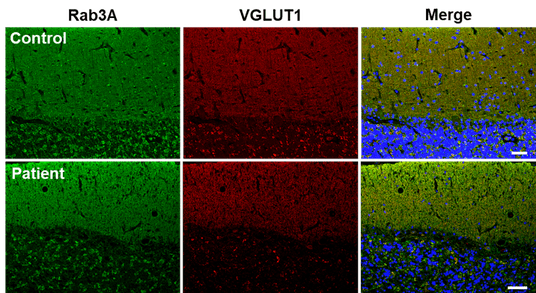

マウス及びヒト小脳の免疫染色により、Rab3Aが平行線維終末に特異的に局在し、プルキンエ細胞側にはほとんど発現しないことを確認しました(図2)。これにより、小脳におけるRab3Aの主な働きの場が平行線維-プルキンエ細胞間シナプスであることが示されました。

(図2)Rab3Aは小脳の平行繊維に局在